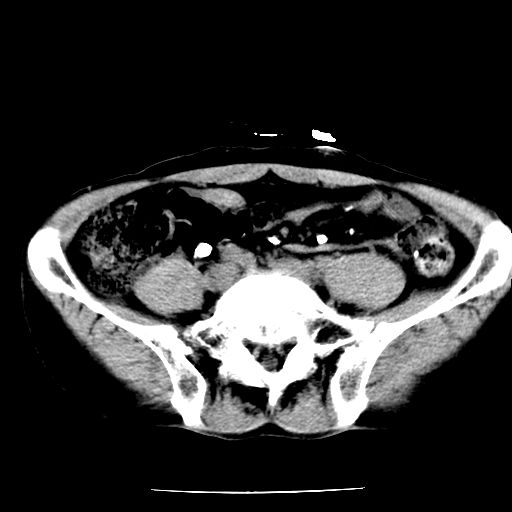

男,59岁,“结核性胸膜炎”30余年,胸部经常疼痛,多次x检查提示“肺部”炎症。腹部疼痛5日,b超提示:“肝内短管结石,余显示不清,建议进一步检查。”

两肺结核并右侧胸腔积液;脾脏、腹腔及腹膜后淋巴结结核[陈旧性];肝内胆管结石

胸部腹部都是结核(双肺。纵隔淋巴结,肝脏,脾脏,肠系膜)